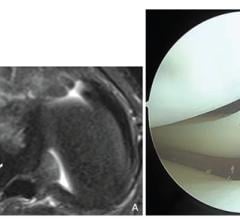

September 24, 2025—According to the American Journal of Roentgenology (AJR), MRI can reliably identify lateral meniscal ...